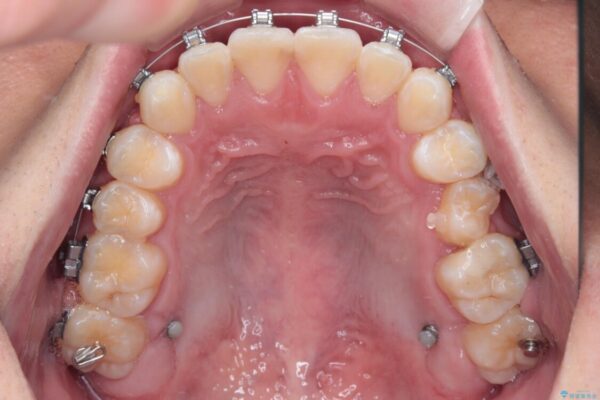

・費用と期間を抑えるために、多少目立っても効率の良いメタルブラケットを使用

・奥歯のシザーズバイト改善には、口蓋側にアンカースクリュー(TAD)を設置し、矯正用ゴムで内側に牽引

・捻転した第二小臼歯は、ワイヤーと矯正用ゴムの力を用いて正しい位置へ回転移動

治療途中

• 前歯のガタガタ・奥歯のかみ合わせ(シザーズバイト)を改善|1年半で完了したメタルブラケット矯正 治療途中画像